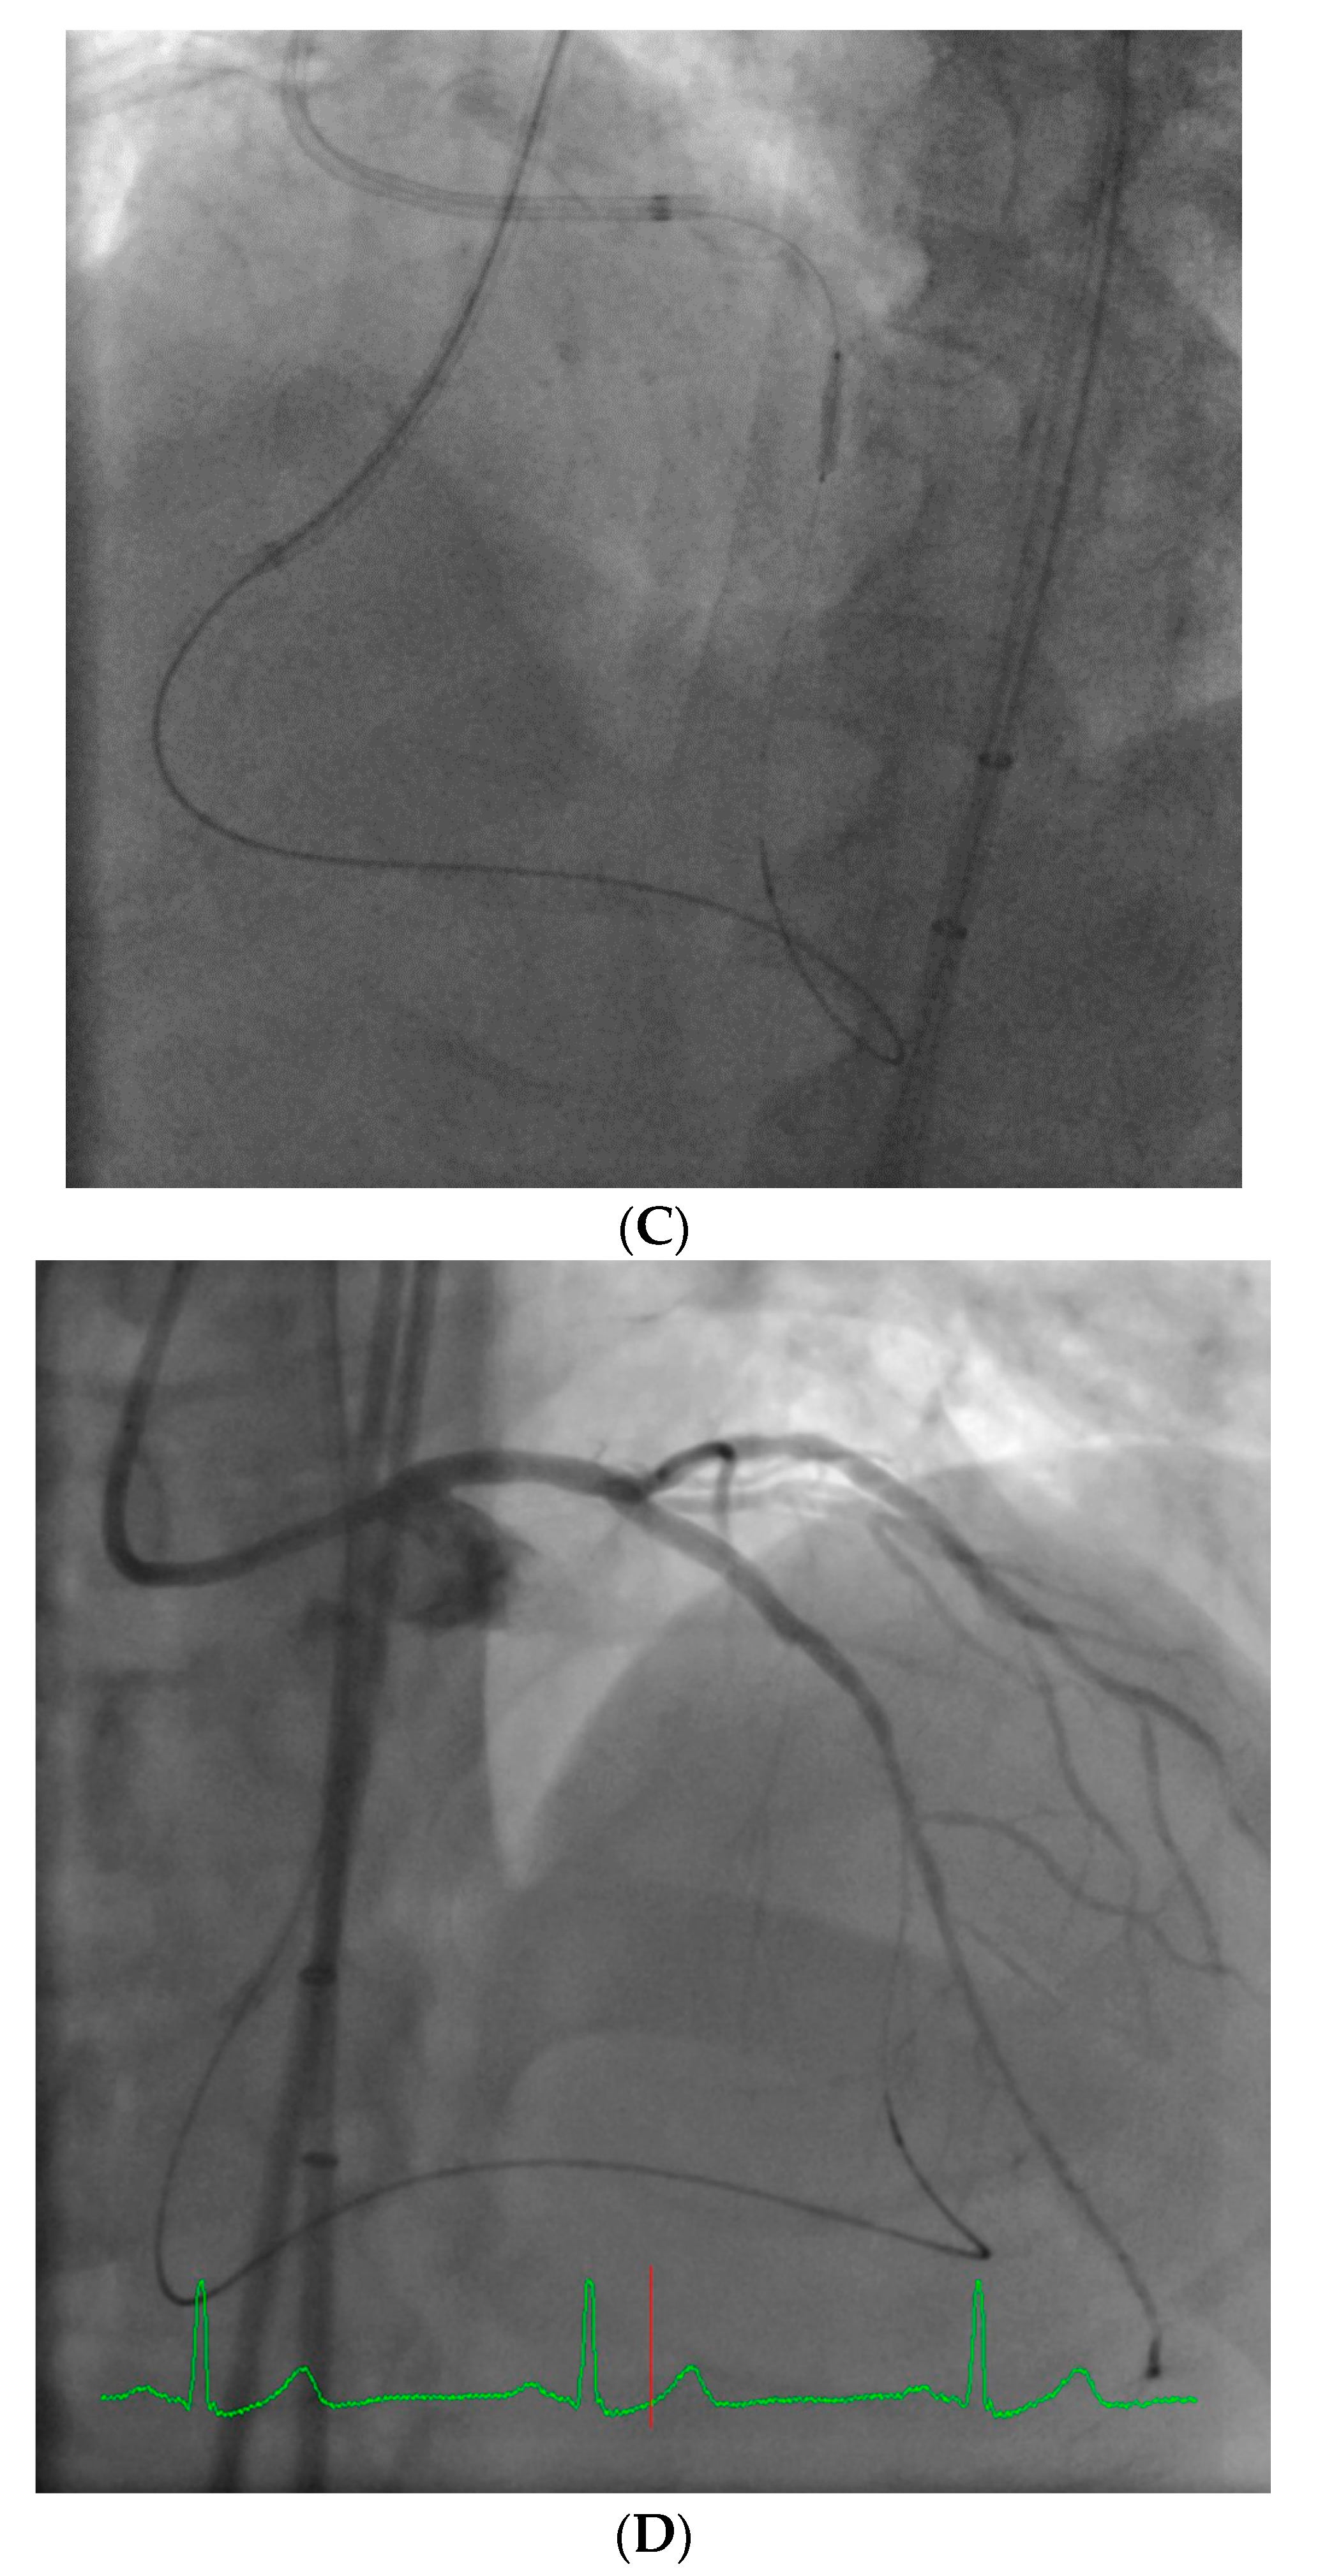

From a pure anatomical standpoint, bifurcation cases with planned kissing stents or kissing balloon angioplasty are not ideal for robotic PCI primarily because the system can only advance one catheter actively. However, bifurcations where provisional side-branch intervention is planned are reasonable choices for robotic PCI. Cases with excessive vessel tortuosity may be successfully performed robotically (Figure 3); however, extreme arterial angulation, or lesions that are severely eccentric or have dissected plaque morphology may require the use of tactile feedback that is not afforded by the robot and are not ideal (Figure 4). Although the advanced wire techniques required for anterograde wire escalation, dissection re-entry approaches, or retrograde approaches in chronic total occlusion intervention are not applicable robotically, we have used the robot to deliver and perform balloon angioplasty, stenting, and post-dilatation after first successfully manually crossing chronic total occlusions with a guidewire (Figure 5). Although the current generation system allows the operator to make fine adjustments in the guide catheter position, ostial lesions, particularly involving the RCA can be very challenging to perform robotically (Figure 6). Finally, cases that require the use of aspiration, atherectomy, filter wires, or certain imaging catheters (OCT and some IVUS), are not suitable for stand-alone robotic PCI.

Figure 3. Example of a complex lesion involving the LAD in a patient with angina and severe tortuosity (A). Despite the tortuosity, the lesion was successfully wired, ballooned, and stented robotically (B). Post stent result shown in (C).